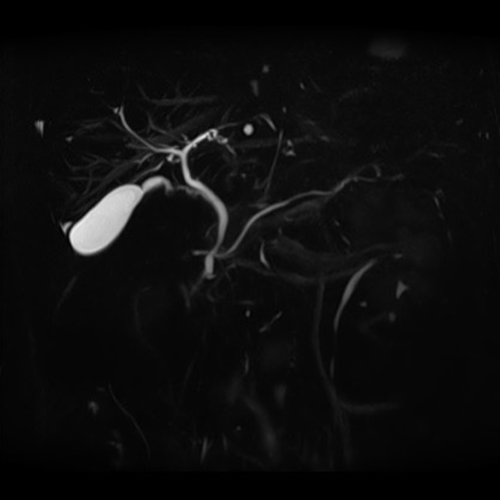

MRI検査とは

CTやX線検査と違い、磁石と電波を使って体の様々な断面像を撮像するので、放射線による被ばくはありません。

造影剤を使用せずに血管を描出することもでき、脳動脈瘤や血管狭窄などの診断に利用されます。また、胆管・膵管・脊髄・尿路なども非造影で検査を行うことができます。

頭部検査においては、特に有用で、CT検査では発見できない急性期の脳梗塞を捉えることができ、早期診断・早期治療を可能にします。この他にも、脊椎・骨軟部・関節・腹部・骨盤腔(子宮・卵巣・前立腺)の病変に優れた描出能があり、様々な疾患の早期発見・診断に有用とされ、研究が進んでいます。

全身DWI

頭部

脳血管像(非造影)

胆管・膵管(非造影)

腹部

乳房DWI